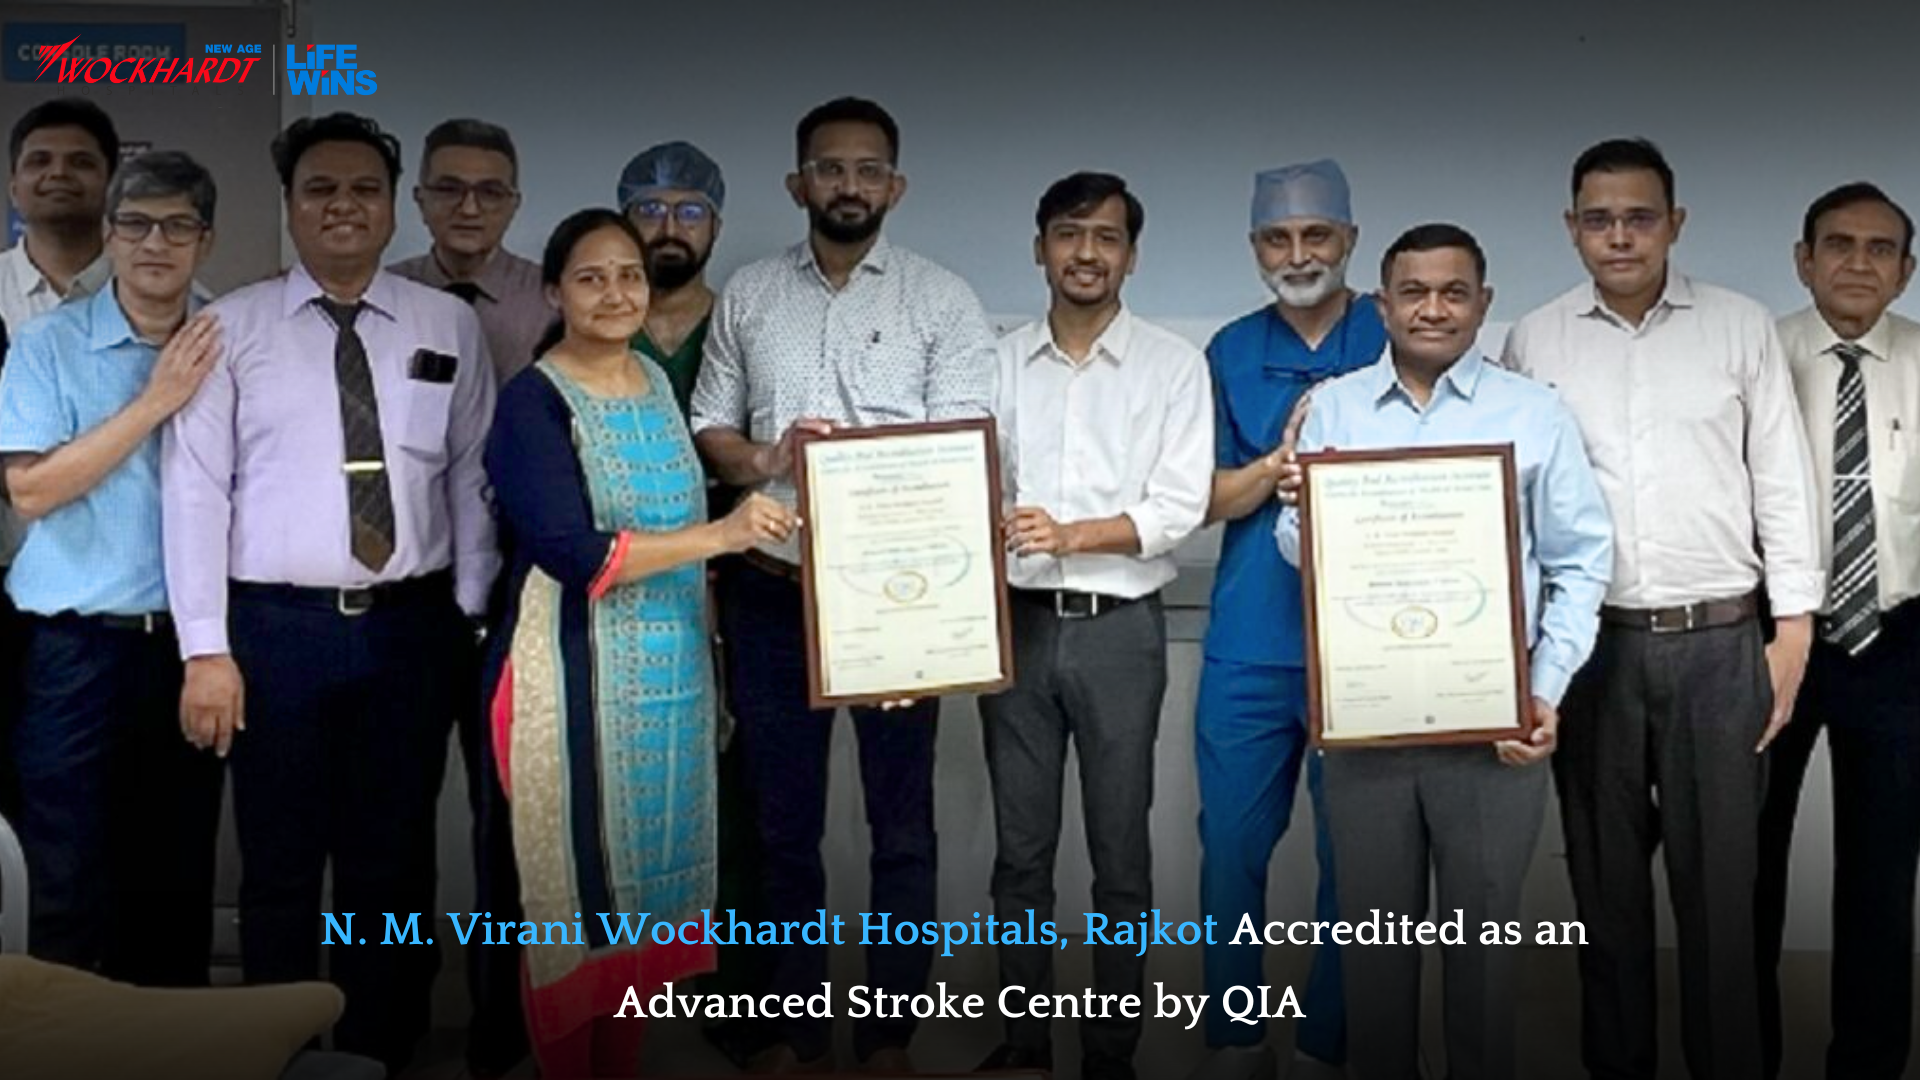

N. M. Virani Wockhardt Hospitals, Rajkot Recognized as Advanced Stroke

Read More